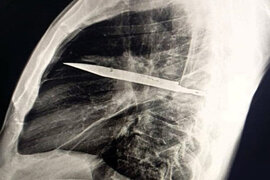

8 il sinəsində bıçaqla yaşayıb: bundan xəbəri olmayıb

Tanzaniyada bir kişi həkimləri heyrətə salıb. Məlum olub ki, o, səkkiz il sinəsində bıçaqla yaşayıb. xarici mediaya istinadla bildirir ki, 44 yaşlı pasiyent sağ döş giləsindən irin gəlməsi şikayəti ilə xəstəxanaya müraciət edib. Həkimlər təəccübləniblər, çünki onun başqa heç bir əlaməti olmayıb. O, sinəsind